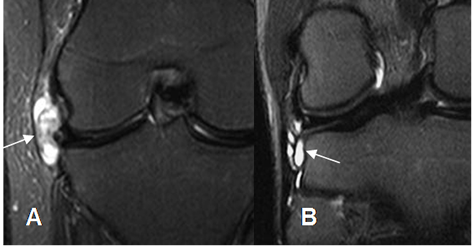

Fig 184. Bursitis lateral.

A y B: RM coronal en STIR. Lesiones por bursitis en relación con el tendón de la banda iliotibial en A y con el tendón del biceps femoral en B.